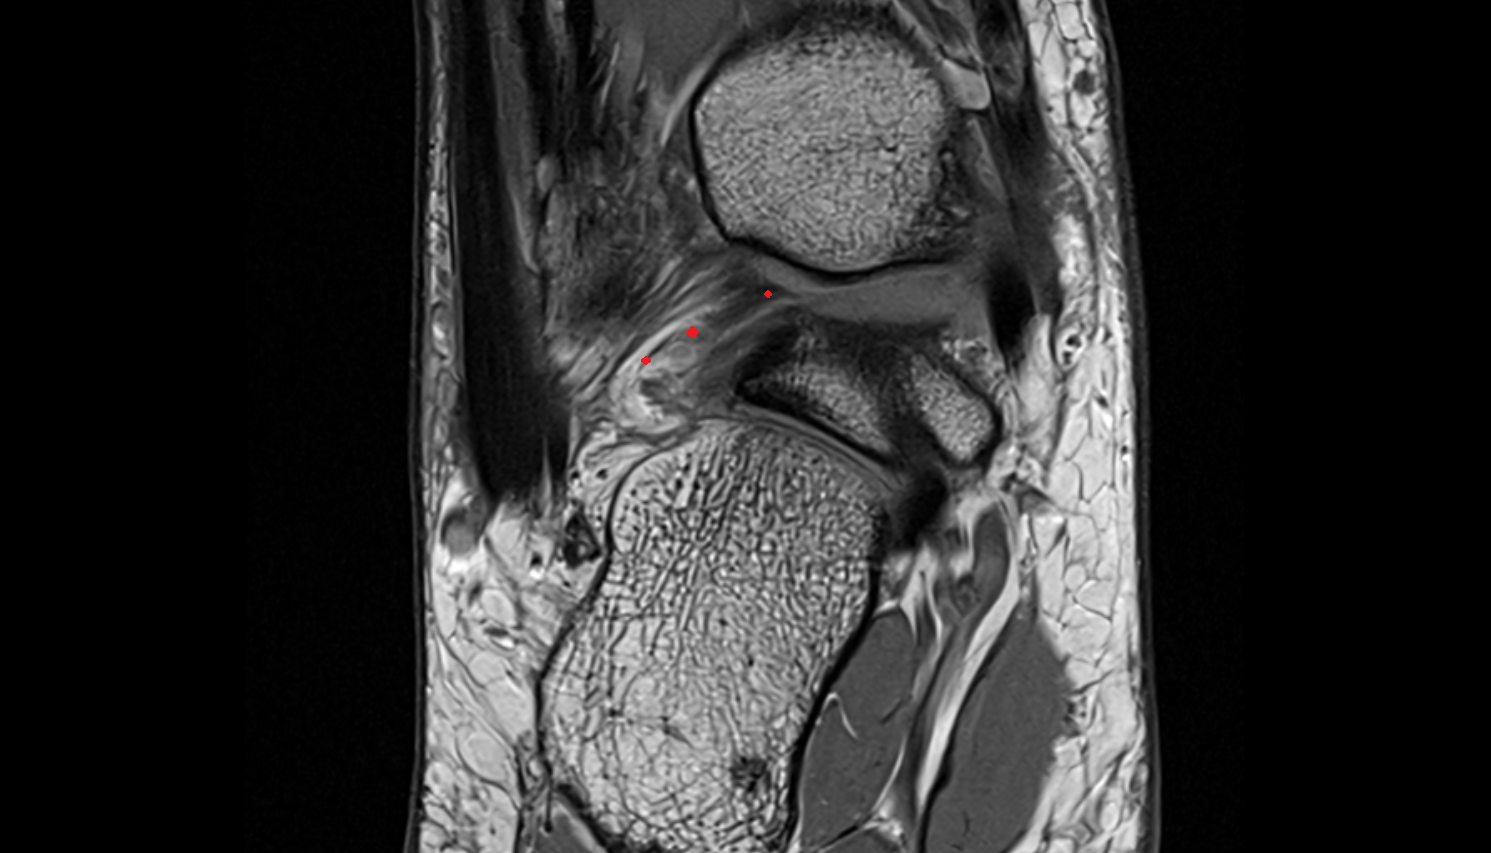

- Anterior cruciate ligament

- Posterior cruciate ligament